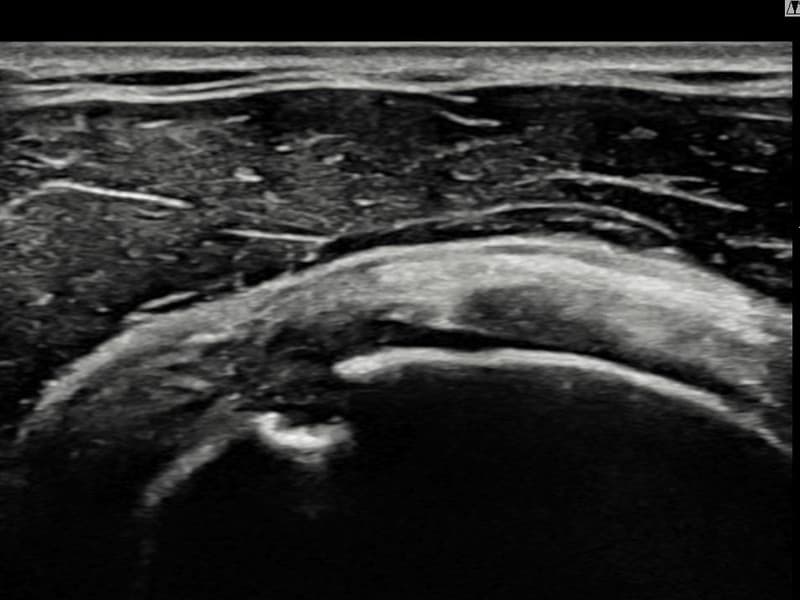

施術前

術前超音波にて右 棘上筋腱 滑液包面側部分断裂・右肩棘上筋腱のエコー不連続と腱欠損(13mm × 6mm (腱厚の約62%欠損))を確認。術後超音波では断裂部位が再生組織で充填され、腱の連続性回復とエコーパターンの正常化が確認されました。